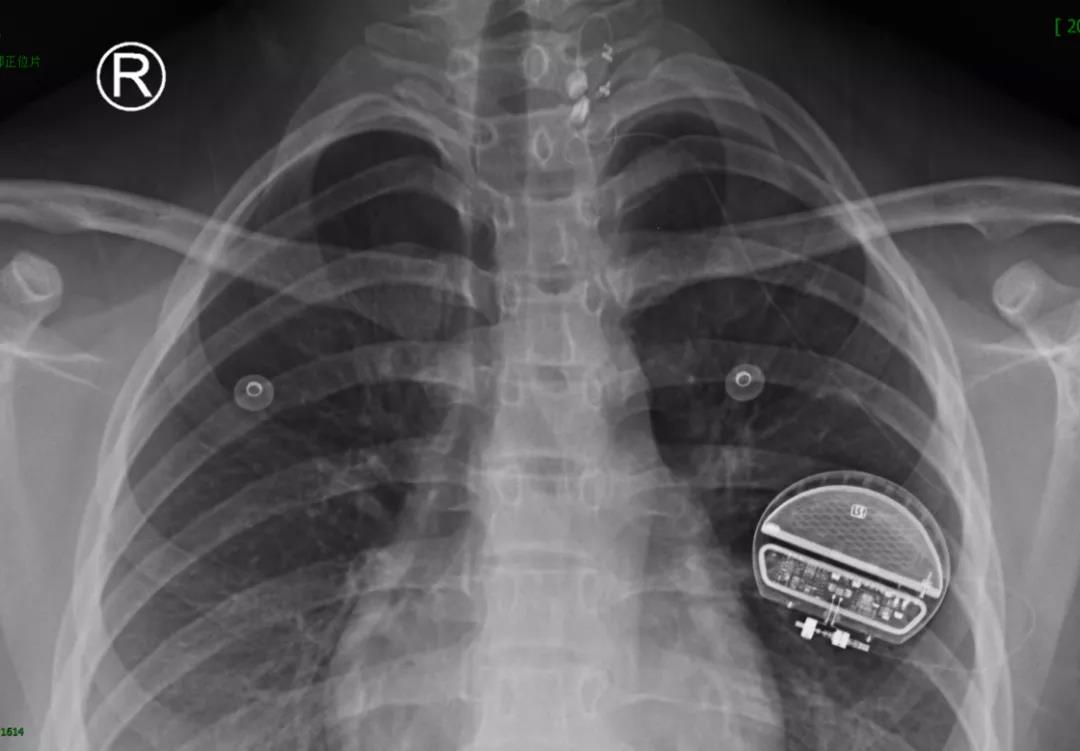

小梁的家长很着急,现在她年龄还小,以后还要面临工作、结婚及生子等生活问题,反复的癫痫发作势必会影响她今后的生活。胡医生想到了迷走神经刺激手术(Vagus nerve stimulation,VNS),也叫电子药物,这种微创手术可以通过电流反复刺激神经,起到控制癫痫发作的作用。小梁做了手术后没有出现任何的不适,病情也得到一定的控制,医生也定期为她进行刺激参数的调整,希望她在未来的生活里一直做个爱笑的姑娘。

迷走神经刺激术(VNS)是同时被美国FDA及欧洲CE认可的,一种辅助治疗难治性癫痫的神经调控方法。当患者不适合手术治疗、不愿进行手术治疗、无法耐受抗癫痫药物且不适合手术治疗、癫痫灶位于功能区、外科手术未能有效控制癫痫发作时,我们建议患者可以考虑VNS治疗。

虽然VNS治疗无法达到完全控制发作,但可减少发作频率或强度、改善患者认知功能,从而提高生活质量;而且刺激时间越长,效果越好。因副作用小,VNS治疗可与抗癫痫药物治疗互补,使更多的不适合手术的药物难治性癫痫患者得到更好的治疗选择。